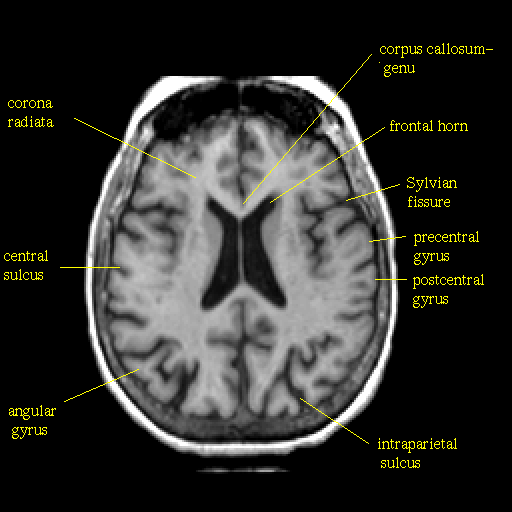

T1-weighted structural MR: Slice 32

Slice 32